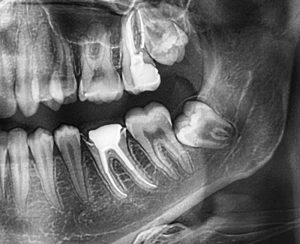

In some cases, wisdom teeth may only partially emerge, leaving a flap of gum tissue covering the tooth. This flap can trap food particles and bacteria, leading to gum infections, further exacerbating the pain and swelling. Impacted wisdom teeth, where the tooth does not have enough space to emerge correctly, can also be a source of discomfort. Impacted teeth may grow at an angle, pressing against other teeth, and potentially causing damage to the surrounding dental structures.

In some instances, individuals may develop cysts or tumours around impacted wisdom teeth, which can lead to further complications and heightened discomfort. If left untreated, these issues can cause damage to the jawbone and other teeth, making prompt intervention essential.